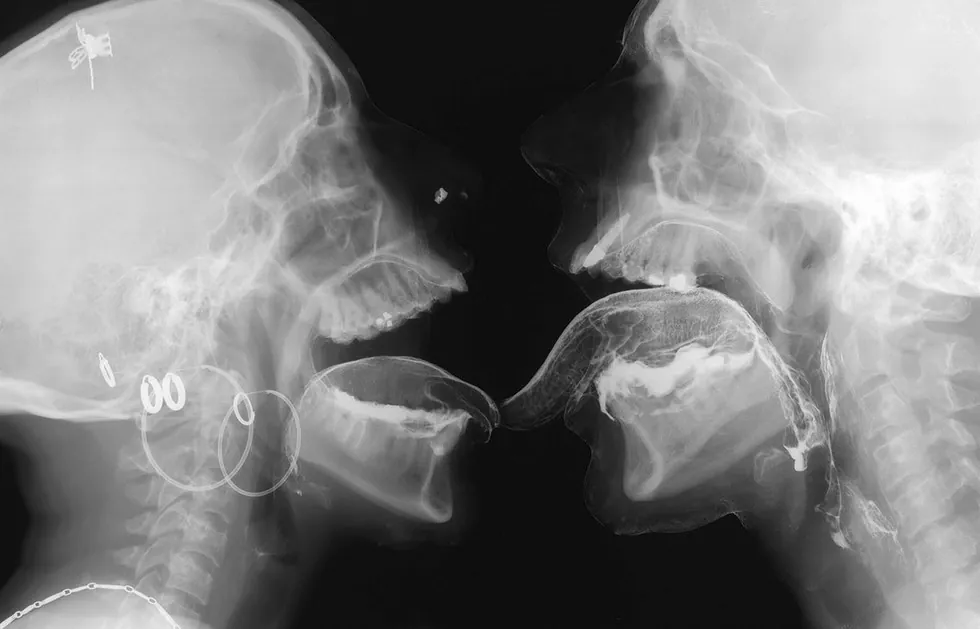

Beginning around 2001, Delvoye initiated Sexrays, a project that involved his first major foray into contemporary radiological imagery. Working with a cooperating radiologist, he arranged for a group of friends to participate in X‑ray sessions inside medical imaging facilities. The participants applied small quantities of barium, commonly used as a contrast agent in radiology, to make certain parts of the body visible during scanning. They then performed intimate physical interactions while being recorded by X‑ray machines. Delvoye observed the process remotely on a computer monitor in another room, allowing the participants enough distance and privacy to behave naturally.

For the stained glass window works, Delvoye used X‑ray images taken during intimate encounters between two friends. The skeletal images produced by the radiographs were incorporated directly into stained-glass compositions and placed within Gothic-style window frames. From a distance the windows appear abstract, their luminous shapes resembling decorative patterns of light and color. Only when viewed closely do the anatomical elements emerge: skulls, teeth, spinal columns, and ribs forming intricate visual arrangements. In some panels the figures are clearly interacting, even kissing.

The imagery itself consists primarily of thousands of individual radiographic frames depicting skeletal structures, spinal columns, skulls, teeth, lungs, and various bodily gestures. In place of saints or biblical scenes, Delvoye created panels so that they would depict skeletal figures embracing, kissing, and interacting within the architectural frameworks of typical Gothic church windows. Yet the images reveal very little of the emotional dimension of human intimacy. Instead, the bodies appear as mechanical structures, bones and joints moving through space, suggesting that radiography reduces the human body to a kind of biological machine.

Delvoye himself has framed the work through a deliberately materialist perspective. “I only believe in what I can see. In my universe there is no soul and there is no love. I’ve never seen the soul and I’ve never seen love. I’ve seen skeletons, teeth, penises, lungs with X‑rays. I’ve never seen love.” The statement captures the conceptual tension underlying the project: the contrast between the invisible emotional meanings normally associated with human relationships and the stark physical evidence produced by medical technology. Despite the nihilistic impression it may convey at first, the works are meant to truly elicit a sense of contemplation.

Within this context the images function almost like contemporary vanitas compositions. In the tradition of seventeenth-century European art, vanitas imagery often used skulls and skeletal motifs to remind viewers of mortality. Delvoye’s X‑rays similarly confront the viewer with skeletal forms that appear simultaneously ghostlike and mechanical. Rather than revealing hidden emotions, the radiographs emphasize the connection between physical desire and mortality, linking sex and death within a single visual structure.